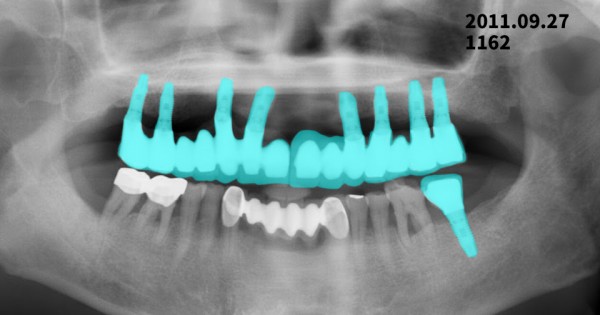

2011년 임플란트 식립 후 2025년 정기검진

2011년: 임플란트 식립 후 파노라마 촬영

???? 상악(윗턱) 임플란트 변화

2011년과 비교했을 때 2025년 영상에서

* 임플란트 나사산 주변 골 접촉 상태가 전반적으로 잘 유지

* 임플란트 목 부위에서 경미한 치조골 흡수는 관찰되나

→ 장기 사용 임플란트에서 흔히 나타나는 생리적 변화 범위

여러 개의 임플란트가 보철물로 연결된 구조로,

저작력 분산이 비교적 안정적으로 이루어진 상태로 판단됩니다.

???? 하악(아랫턱) 임플란트 변화

* 좌·우 하악 후방 임플란트 모두

2011년 대비 치조골 높이 변화가 크지 않음

* 임플란트 주위에 염증을 의심할 만한

뚜렷한 방사선 투과성 소견은 보이지 않음

???? 임플란트 주위염(peri-implantitis)을 강하게 의심할 소견은 없는 상태입니다.